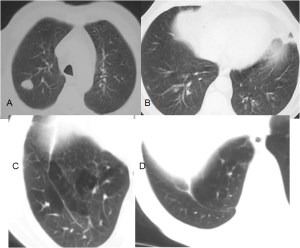

SIGNO DEL CASQUETE APICAL IZQUIERDO

La aparición de una densidad en el ápex pulmonar izquierdo, de borde inferior cóncavo y bien delimitado (casquete apical) en un paciente con traumatismo torácico, debe hacernos sospechar la existencia de una rotura aórtica.

Deben excluirse otras causas de casquete apical, especialmente las lesiones residuales tuberculosas, que suelen acompañarse de otros hallazgos como tractos fibrosos pleuro-parenquimatosos, pérdida de volumen en el lóbulo superior, granulomas, etc.

Mostramos un caso de rotura aórtica por accidente de moto. En este paciente también aparece el signo de la alteración del contorno aórtico.

En el corte de TC de tórax con contraste intravenoso del mismo paciente vemos la rotura aórtica (flecha verde), un hemotórax bilateral –algo más cuantioso en el hemitórax izquierdo- (flechas azules) y un hematoma mediastínico (flecha naranja).